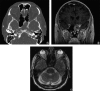

Clinical experience has suggested the existence of an intermediate form of fungal sinusitis between the categories of non-invasive fungal sinusitis (non-IFS) and invasive fungal sinusitis (IFS). This fungal sinusitis variant demonstrates unhealthy mucosa by endoscopy with fungal invasion, but lacks angioinvasion microscopically, representing what clinically behaves as a 'pre-invasive' subtype of fungal sinusitis. Unlike non-IFS disease, patients with pre-invasive fungal sinusitis were still felt to require anti-fungal medications due to histologic presence of invasive fungus. While sharing some clinical features of IFS, these 'intermediate' patients were successfully spared extended and repeated surgical debridements given the microscopic findings, and have been successfully treated with shorter courses of antifungal therapy. These select patients have had favorable outcomes when managed in a judicious and semi-aggressive manner, in an undefined zone between the treatments for routine fungal ball and aggressive IFS.